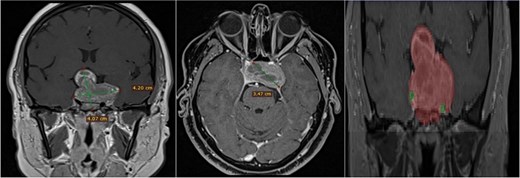

Contrast-enhanced T1 MRI of pituitary marcoadenoma. Multiplanar conventional geometric volumetry.

Manual planimetric volumetric segmentation. (A) Calculation of total tumor volume (red) and its relationship with the internal carotid artery (green). (B) Volumetry by zones. (C and D) Areas shown in sagittal and coronal planimetry.

A 42-year-old patient who suddenly presented with headache and visual disturbances. The examination confirmed bitemporal hemianopsia, as well as bilateral papilledema. An MRI study obtained the following sequences: T1, T2, and T1 with contrast (Fig. 4). Manual 3D segmentation was performed to observe the intratumoral components and classify the different anatomical portions of the tumor, as well as its total estimated tumor volume and area (Fig. 5 and Table 2). The importance of reconstruction, in this case, lay in knowing the areas that were possibly not going to be so easily accessible through this endoscopic approach, as well as in calculating the volume of the tumor per segment and the possibility of having residual tumors in less accessible segments.